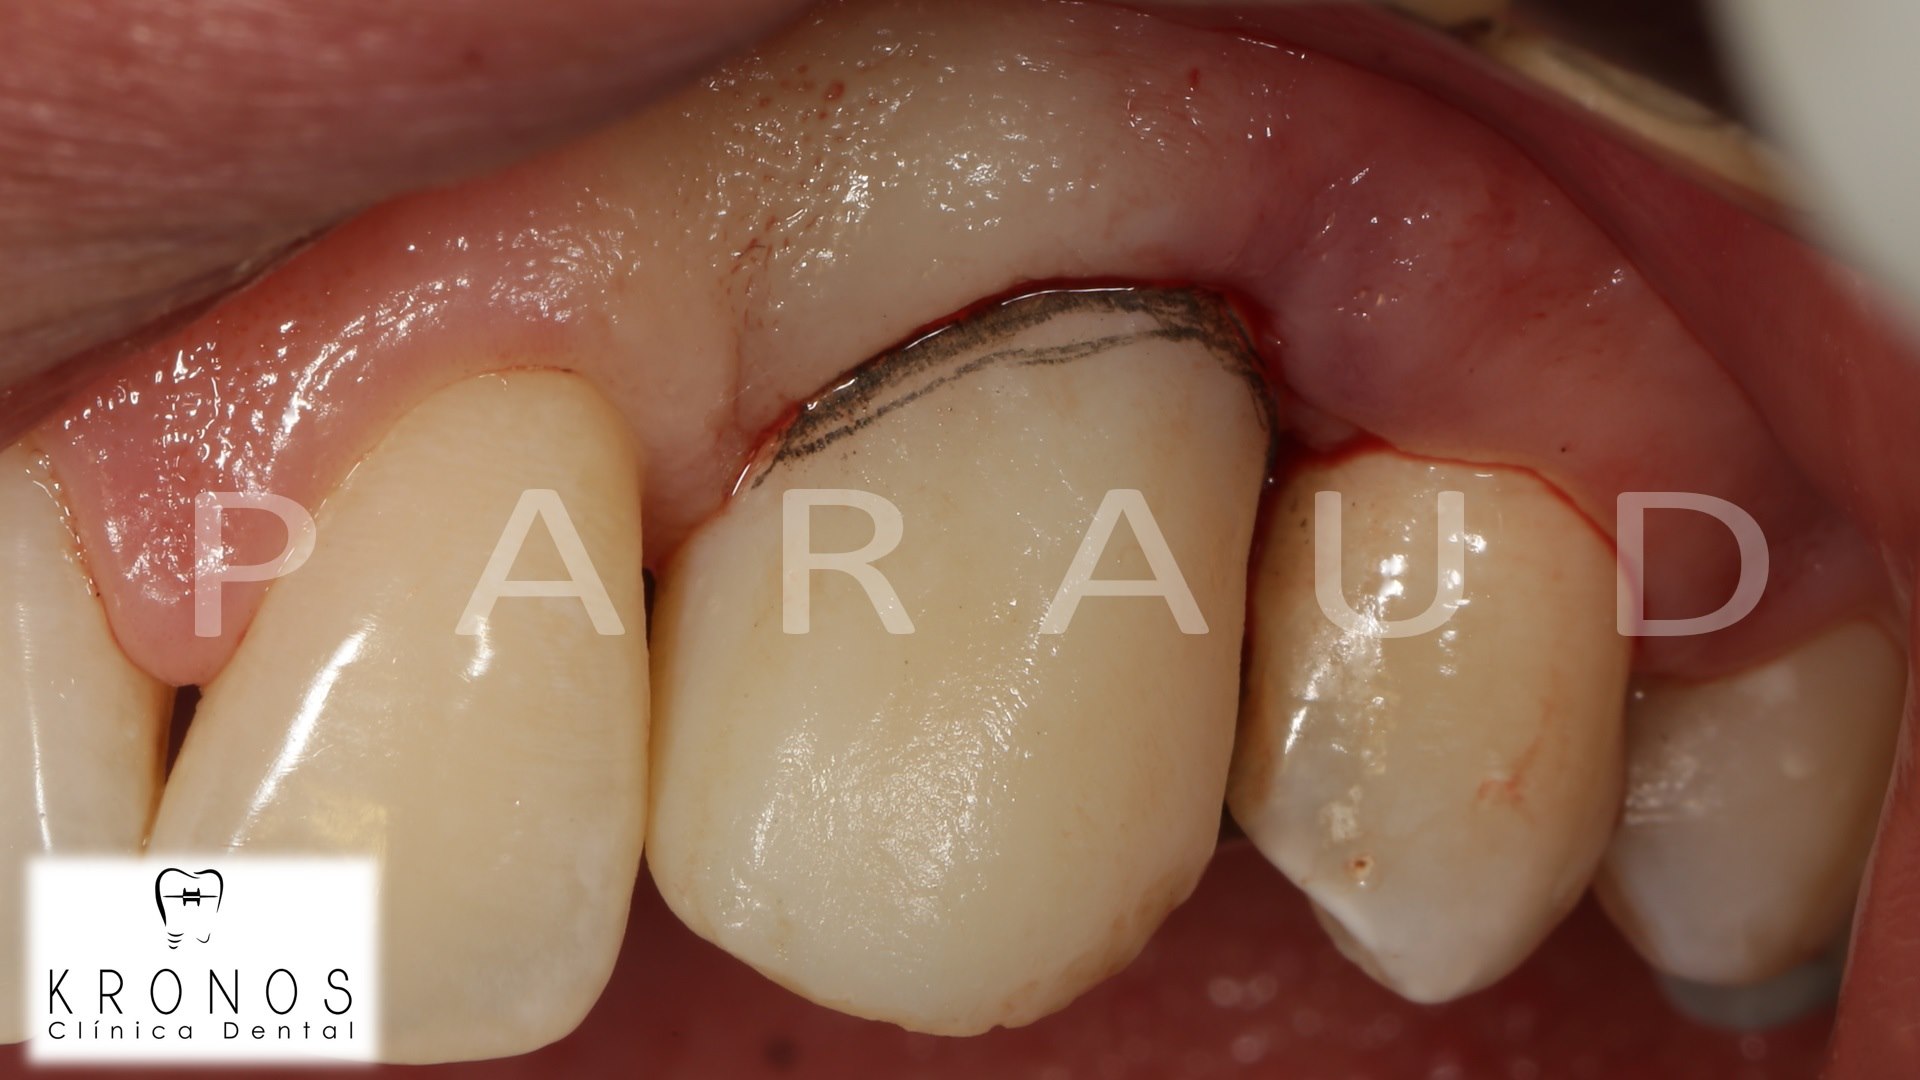

Clinical case: AnyRidge immediate loading

- Courtesy of Dr. Andres Paraud Freixas, Chile -

AnyRidge, ISQ value, initial stability, immediate loading, KnifeThread, maxillary anterior, Mega ISQ, Dr. Andres Paraud Freixas

AnyRidge implant system, Mega ISQ, Digital prosthesis